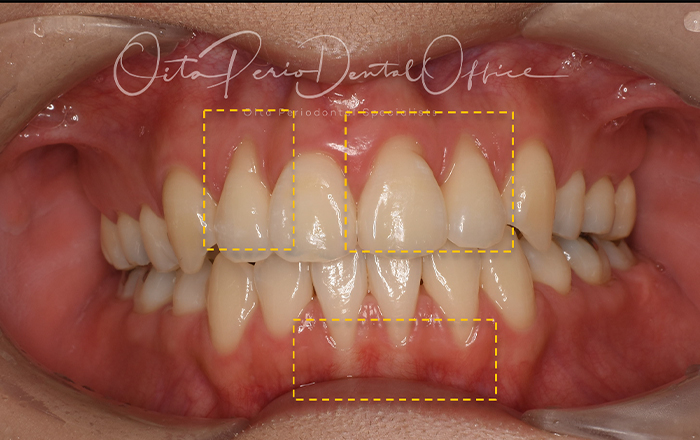

| 治療期間 | 6週間 |

|---|---|

| 治療費 | 13万(手術が2回の場合は26万) |

| 治療内容 | 右下3・4、左下2・3・4根面被覆(結合組織移植術) |

| 治療のリスク | ドナーサイトが必要、術後の疼痛・腫脹、術後の注意事項をフォローしない場合は失敗の可能性あり |